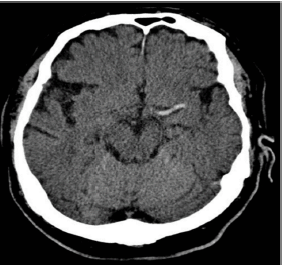

Paciente de 66 anos do sexo feminino com antecedente de hipertensão, AVC hemorrágico há 2 anos sem sequelas, e arritmia, sem seguimento médico adequado, fazendo uso irregular de captopril. Além disso, apresentou traumatismo craniano leve na semana passada, sem maiores repercussões.

Procura pronto-socorro com queixa de déficit neurológico agudo, com aparecimento há 40 minutos. À admissão, exibe PA 150x92, FC 77, FR 18, SatO2 96% a.a., glicemia capilar de 90mg/dL. Ao exame neurológico, apresenta hemiplegia à direita, afasia global e paralisia facial de padrão central, com NIHSS = 15. Realizada TC de crânio, abaixo:

Neste momento, a conduta mais adequada para essa paciente seria